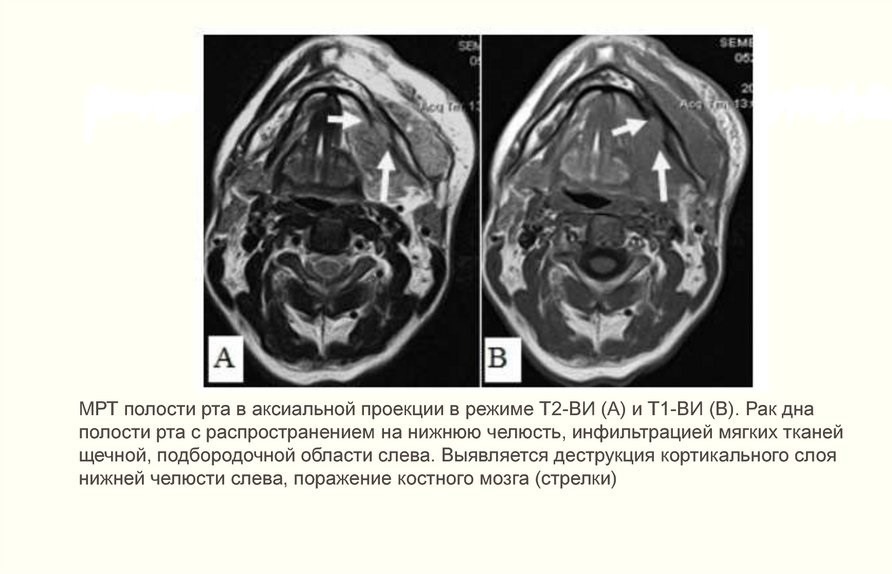

- МРТ и УЗИ мягких тканей шеи. На снимках выявляется локализация патологии, глубина прорастания и структура опухоли, уплотнение из крови и лимфы, разложение коркового слоя кости;

- КТ костей лица с контрастом. Снимки показывают прорастание опухоли в шейные сосуды, челюсть или основание черепа.